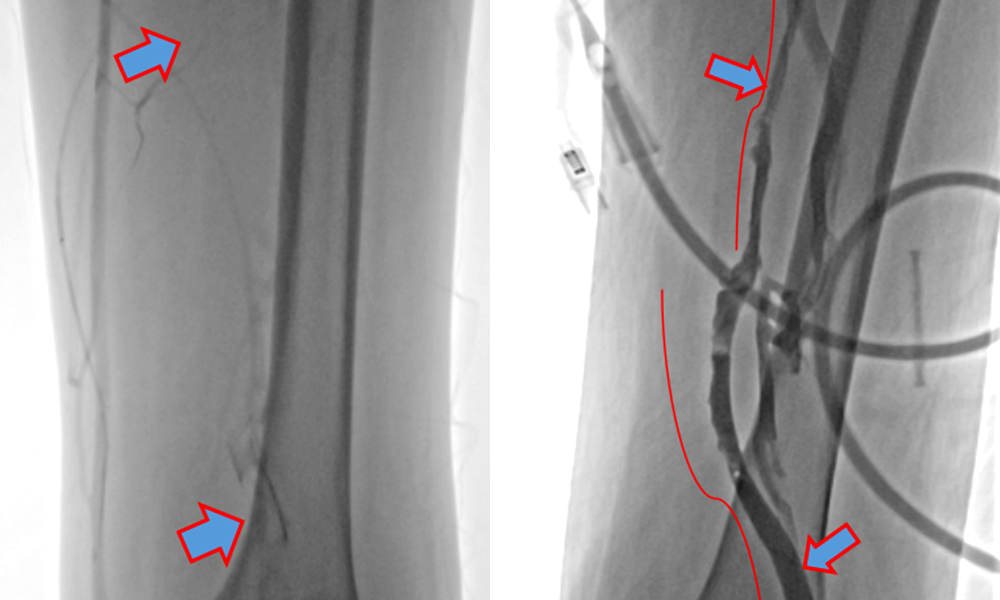

但这次我们用了PMT经皮机械取栓术

半小时就把血栓清得干干净净

✅精准清除:实时影像引导,直达血栓部位,保护血管壁;

✅高效再通:机械碎栓+负压吸引双效合一,迅速恢复血流;